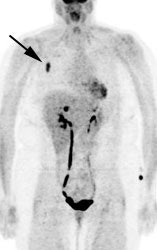

Osseous lymphoma: Unsuspected focal osseous involvement of the femurs was identified on PET imaging of this patient with newly diagnosed B-cell non-Hodgkin's lymphoma (black arrows). Extensive hepatic involvement was seen within the abdomen, but there were no other sites of bone disease. Focal bone disease such as this will not be detected on bone marrow biopsy. |

|

In one study, PET imaging revealed osseous involvement not detected on bone marrow biopsy in 12.8% of patients [6]. This finding resulted in an increase in patient stage in 10% of patients [6]. In that same study, bone marrow biopsy revealed tumor involvement in 5% of patients that was not detected by FDG-PET imaging [6]. However, the cases in which FDG-PET was false negative involved low- or intermediate-grade lymphomas with only discrete displacement (up to 10%) of normal marrow [6]. Because the degree of FDG uptake declines in a lower grade of malignancy -- the combination of lower numbers of malignant cells and low FDG tumor uptake likely resulted in low marrow activity [6].